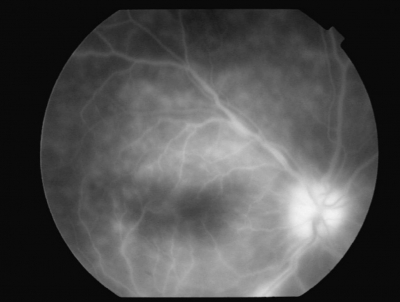

視力は右 0.1(0.2× -2.5 D)、左 0.1(1.0× -2.0D)。右眼の前眼部写真、眼底写真及び蛍光眼底造影写真を別に示す。